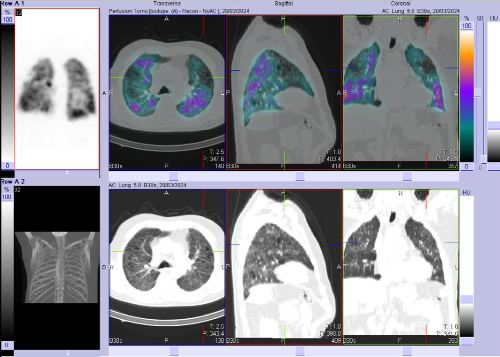

/ Obr. č. 2-7: SPECT/CT plic se zaměřením na vícečetné perfuzní defekty v obou plicních křídlech.

Na scintigramech pozorujeme vícečetné perfuzní defekty v obou plicích (v horním a dolním laloku pravé plíce a v horním a dolním laloku levé plíce). Dále je homogenní distribuce ventilace v obou plicích.

SPECT/CT potvrzuje tyto perfuzní defekty. Na ldCT je dále patrná Vámi popisovaná nespecifická intersticiální pneumonie, taktéž emfyzém, to však nevysvětluje diskrepanci mezi perfuzí a ventilací. Jde tedy o tzv. V/P mismatch.

Závěr: vícečetné perfuzní defekty v obou plicích (v horním a dolním laloku pravé plíce a v horním a dolním laloku levé plíce). Homogenní distribuce ventilace v obou plicích. V/P mismatch.

Nález svědčí pro plicní embolizaci do obou plicních křídel.